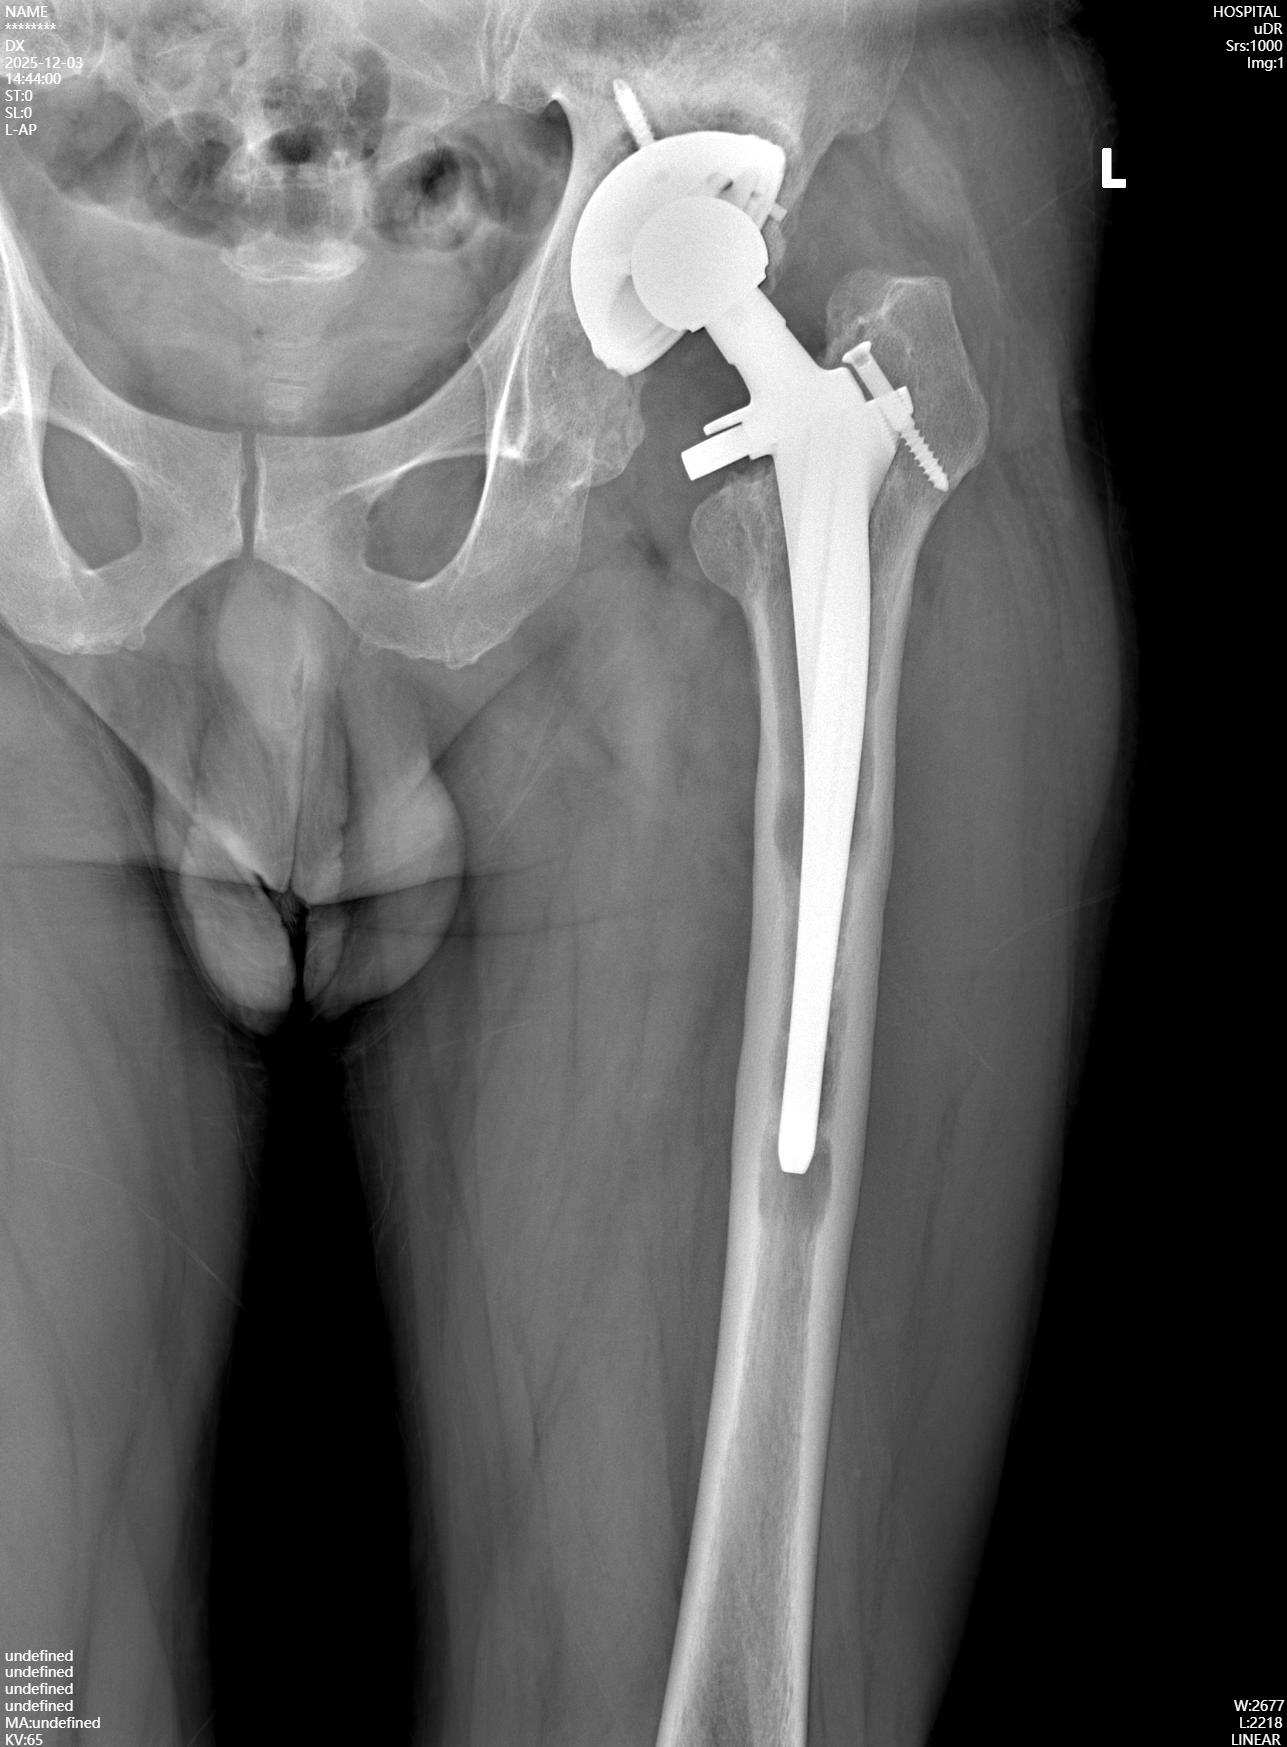

病例資料:患者男,51歲,男性,因“左髖關節(jié)置換術后20年,酸脹不適1年余”入院?;颊?0余年前因股骨頭壞死后行左髖關節(jié)置換手術,術后恢復良好,可恢復日常勞動及一般運動,愛好登山活動,無明顯外傷史。1年余前開始出現(xiàn)左髖部酸脹不適,下肢不敢發(fā)力,并且逐漸出現(xiàn)跛行。入院查體:雙下肢不等長,骨盆向患側傾斜,髖部無明顯腫脹,腹股溝區(qū)壓痛,患側髖關節(jié)過屈時,疼痛稍加重,患側4字征試驗(+),患側滾原木測試(-),患側髖關節(jié)屈伸活動無明顯受限,患側下肢肢端感覺血運未見明顯異常。

入院X線檢查提示:左髖關節(jié)假體松動,髖臼假體及旋轉中心上移,假體周圍可見明顯的透亮線。入院診斷:左側人工髖關節(jié)置換術后假體松動。入院后在髖關節(jié)超聲引導下進行左髖關節(jié)穿刺,穿刺液體進行常規(guī)檢查未見感染征象,血沉及CRP正常,因此屬于無菌性假體松動。

完善術前準備后,擇期行左側人工髖關節(jié)翻修術,術中發(fā)現(xiàn)左側髖臼假體上移,原有的髖臼中心已被疤痕組織填充,取出髖臼周圍出現(xiàn)深灰色的金屬細微顆粒,取出髖臼假體后出現(xiàn)髖臼頂部骨質缺損。股骨側假體也出現(xiàn)松動,股骨柄遠端未見明顯骨長入。

取出假體后,在髖臼頂部缺損處采用金屬墊塊填充后可穩(wěn)固安裝髖臼臼杯,完美恢復髖臼的旋轉中心;股骨側采用組配式假體、遠端早期獲得穩(wěn)定。術中仔細進行止血處理,修復周圍切開的軟組織,術中充分止血后不放置引流管。術后第一天扶雙側拐杖下地行走,恢復良好。